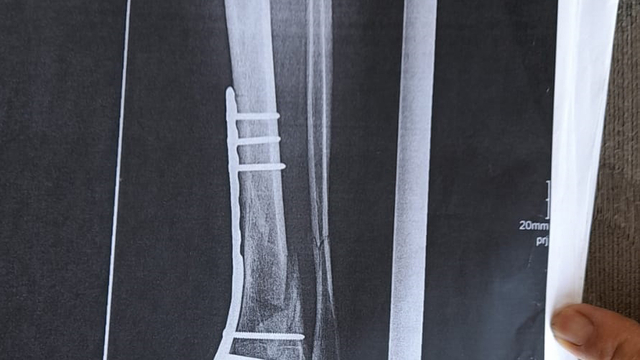

‘DEMİR VAR AYAĞIMDA, SAKAT BIRAKTILAR'

Olay yeriyle ilgili fotoğraf ve görüntüleri mahkemeye sunduklarını kaydeden Güray, "Ömrümü yediler, demir var ayağımda, sakat bıraktılar. Ayağı keseceklerdi neredeyse. Şu an kalıcı sakatlık var. 1 sene kendime gelemedim, 2 haftada bir ameliyata giriyordum. Almanya'da 3 ay hastanede kaldım ve ayağımda yüzde 3'lük engel oluştu" diye konuştu.

Tazminat miktarını düşük bulan Yunus Güray, şunları söyledi: "Benim uçak masrafım sadece 22 bin avro tuttu. 9 yıl oldu, bir tane çukur değildi. Adamlar kazmış, kazmış, bırakmış. Tam merkezde bu olay, hani ormanda bir yerde olur, 'Tamam benim de hatam var. Gittim de düştüm' derim. Ama şehrin merkezinde, etrafı çevrili değildi. Yemyeşil alan, gece vaktiydi. Ben mahkemeye verdim, o çukurları 3 ay sonra kapattılar. 6- 7 yerde kazılmış çukurlar vardı. Bir tane değildi. Ayağımda hala demir var. Adil bir karar olmadı."